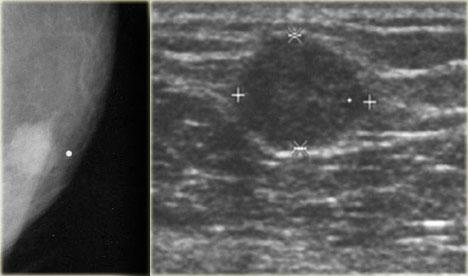

Bên trái là một trường hợp u cơ xơ bào khác.

Núm vú được đánh dấu và tổn thương không nằm ở vùng sau núm vú.

Trên hình ảnh siêu âm, tổn thương khó phân biệt với mô mỡ xung quanh.

Ngay cả khi tổn thương này nằm sau núm vú, bạn cũng không nên chẩn đoán đây là vú to nam giới, vì đây là một khối có múi.